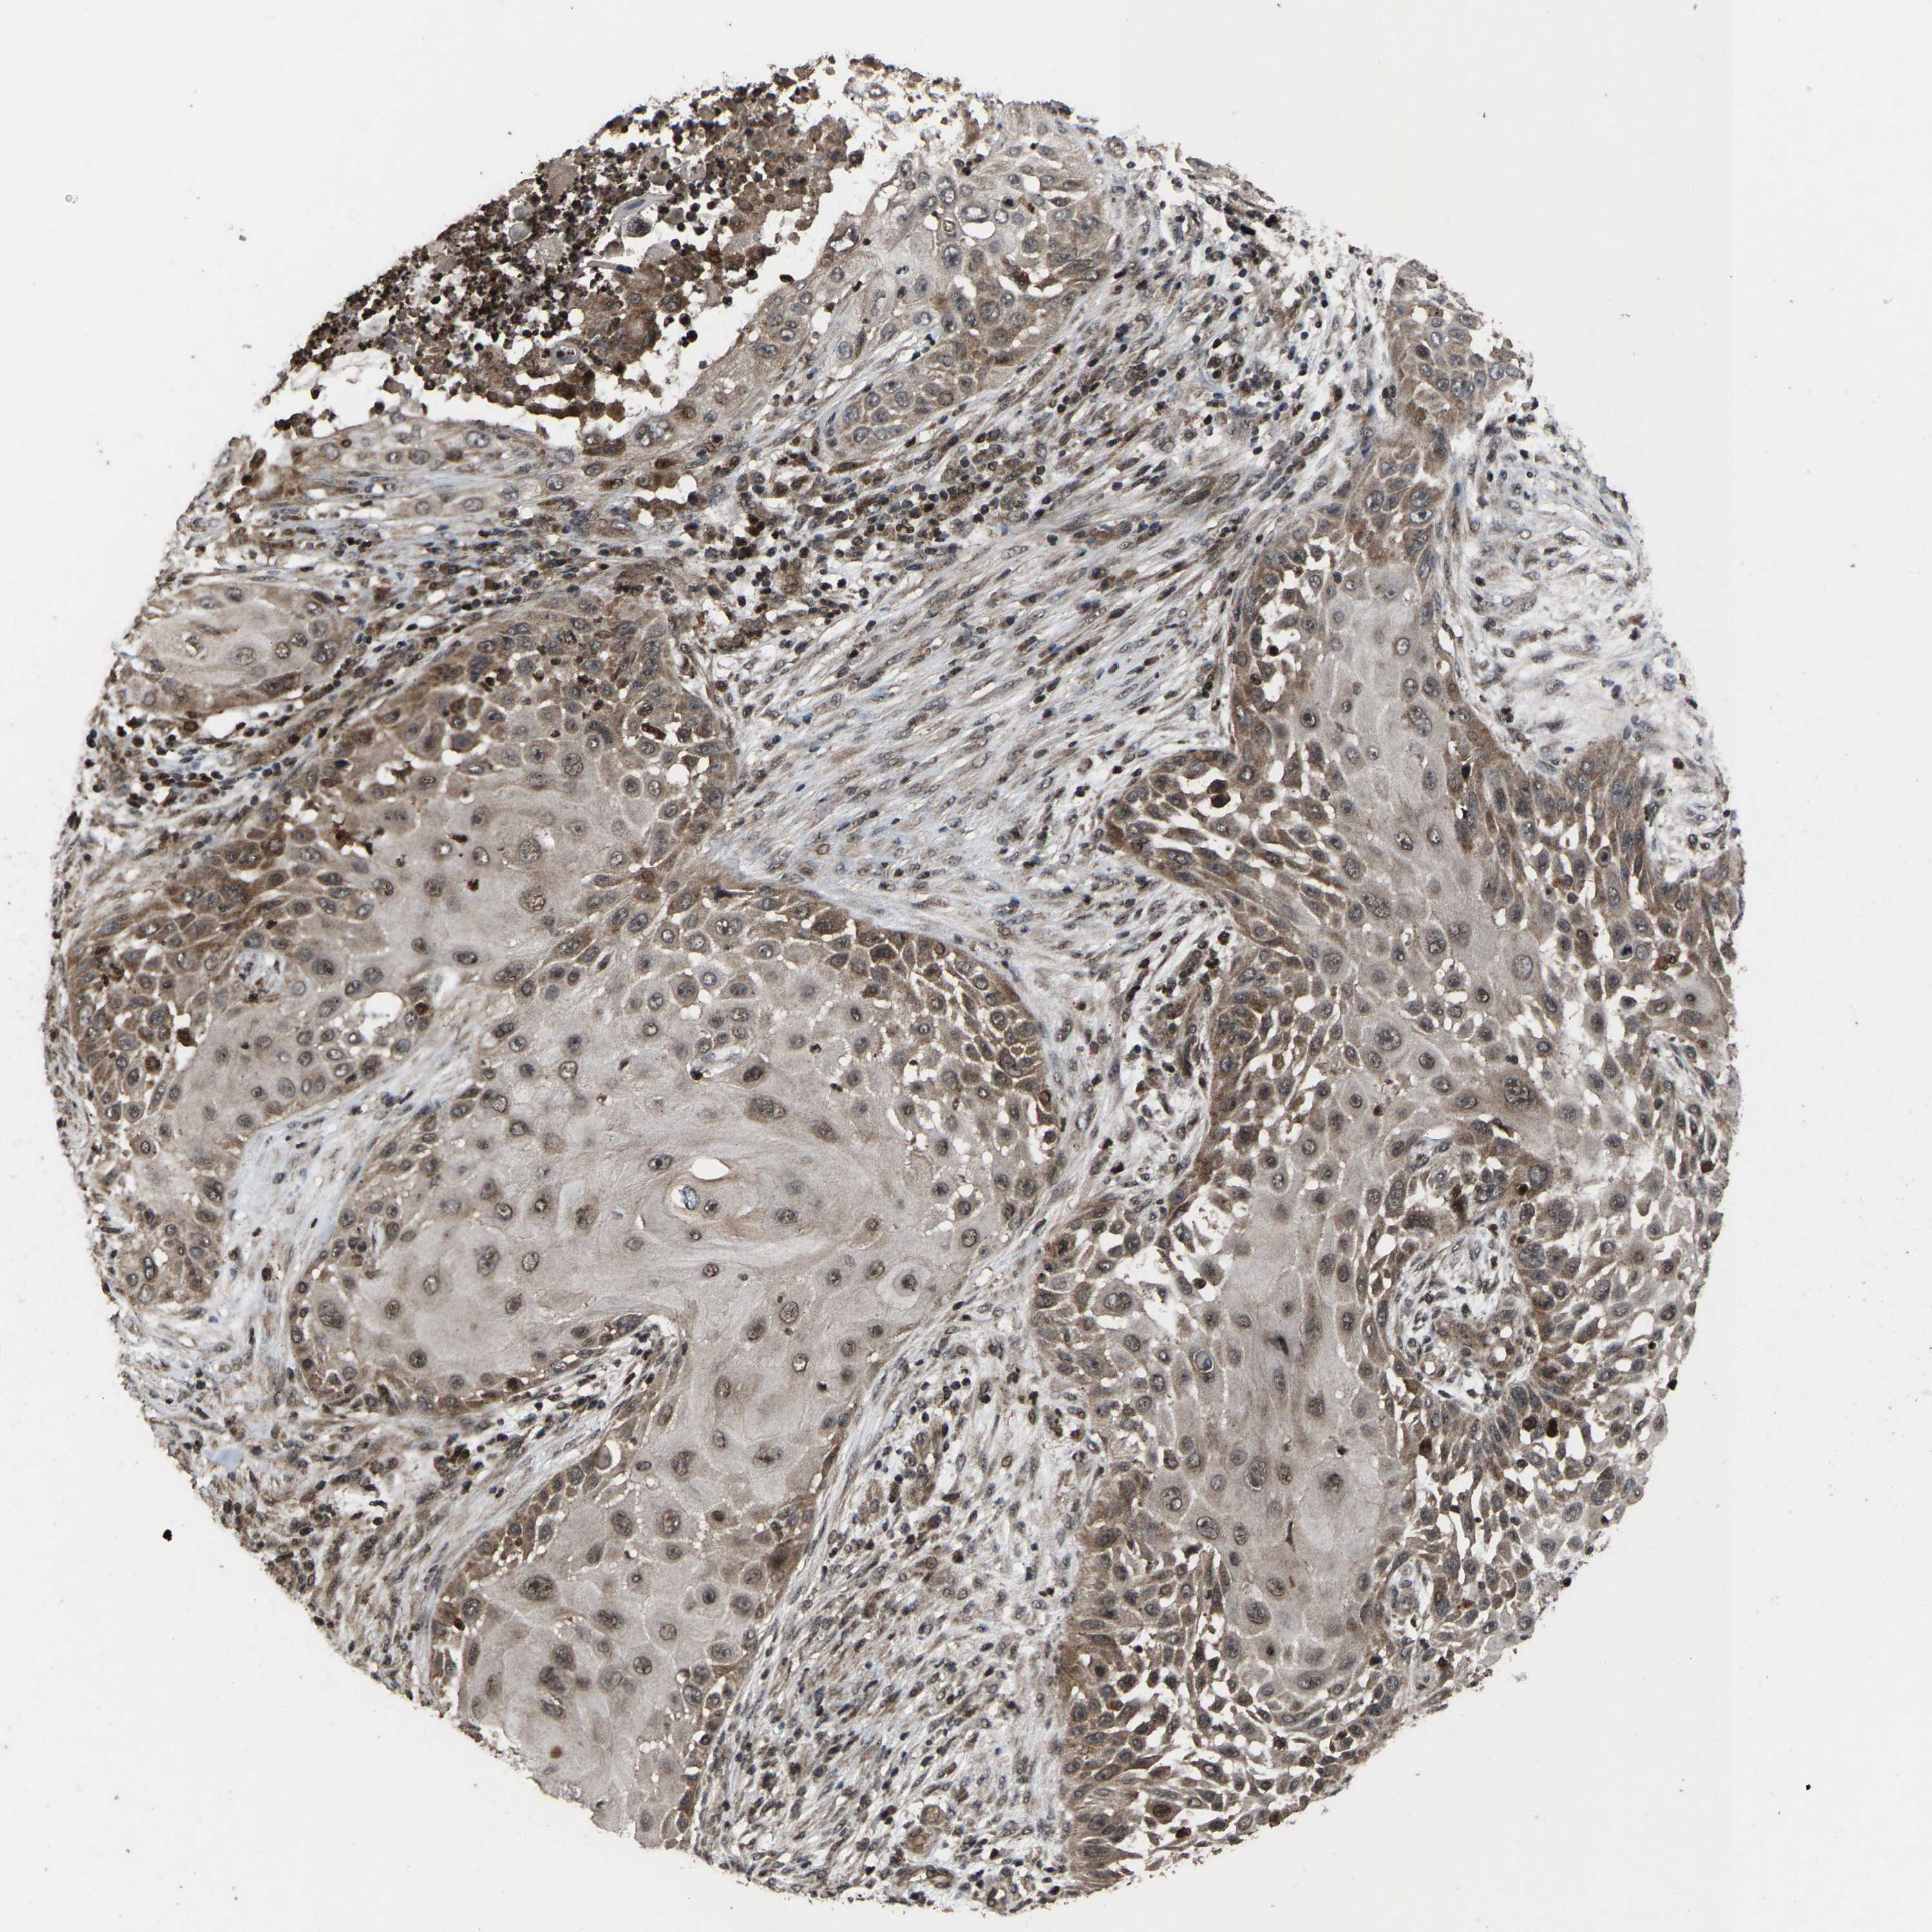

Basal cell and squamous cell cancer

SKIN CANCER - Protein expressioni

A mouse-over function shows sample information and annotation data. Click on an image to view it in a full screen mode. Samples can be filtered based on level of antibody staining by selecting one or several of the following categories: high, medium, low and not detected. The assay and annotation is described here.

Antibody stainingi

Antibody staining in the annotated cell types in the current human tissue is reported as not detected, low, medium, or high, based on conventional immunohistochemistry profiling in selected tissues. This score is based on the combination of the staining intensity and fraction of stained cells.

Each image is clickable and will lead to virtual microscopy that enables deeper exploration of all samples and also displays staining intensity scores, fraction scores and subcellular localization as well as patient and tissue information for each sample.

Antibody HPA020960

Antibody HPA020965

Staining

High

Medium

Low

Not detected

Intensity

Strong

Moderate

Weak

Negative

Quantity

>75%

75%-25%

<25%

None

Location

Nuclear

Cytoplasmic/membranous

Cytoplasmic/membranous,nuclear

Basal cell carcinoma

Squamous cell carcinoma, NOS

Squamous cell carcinoma, metastatic, NOS